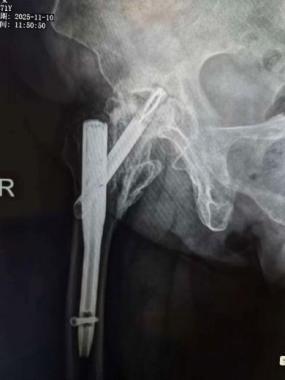

此次入院前X线片及CT

怀着最后一线希望,谈大妈与家属慕名来到陕西省核工业二一五医院创伤骨科寻求诊治。吴超副主任医师接诊后,立即为谈大妈安排了详细且全面的检查,经影像检查发现,虽然粗隆间骨折已愈合,但此前植入的部分内固定物竟突破了股骨头、侵入髋臼,导致股骨头已坏死变形、髋臼骨质缺损。

“这是内固定术后严重的并发症,如不及时干预,患者将永久丧失行走功能。”王争刚主任医师一针见血地告诉家属。